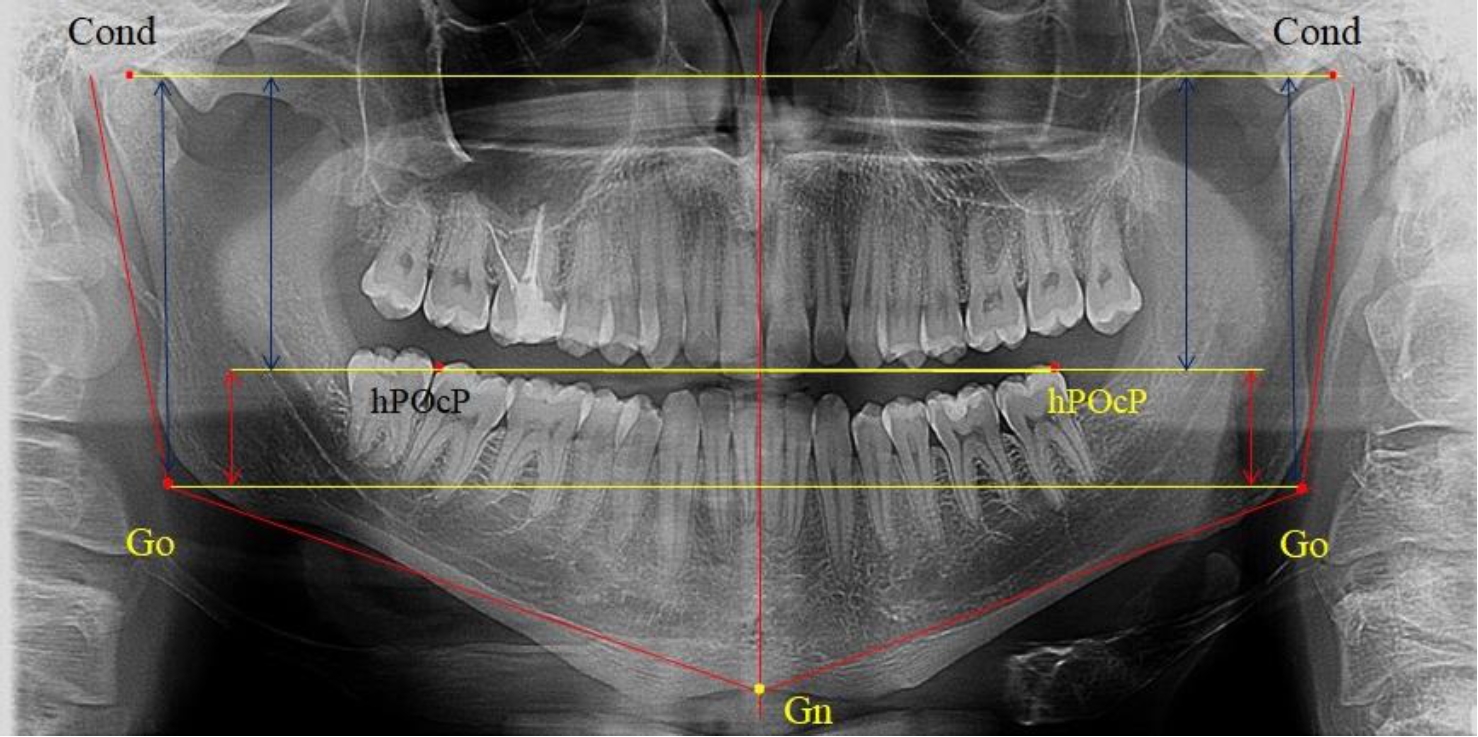

В 1-ю подгруппу были включены 36 комплектов телерентгенограмм и ортопантомограмм [или (48,65 ± 5,81) % от общего количества], на которых средняя величина отношения верхней части ветви к нижней составляла 1,95 ± 0,03, что соответствовало показателям, полученным по группе в среднем, но с меньшим показателем ошибки среднего значения. Визуально верхняя окклюзионно-суставная часть выглядела вдвое больше нижней окклюзионно-гониональной (рис. 2). При этом высота ветви составляла (62,09 ± 1,22) мм. Максимальная высота была 71 мм, а минимальная – 55 мм. Высота верхней части составляла (41,02 ± 0,77) мм, а высота нижнего отдела ветви была (21,09 ± 0,51) мм.

Рис. 2. ОПТГ пациента 1-й группы с оптимальным коэффициентом соотношения частей ветви нижней челюсти